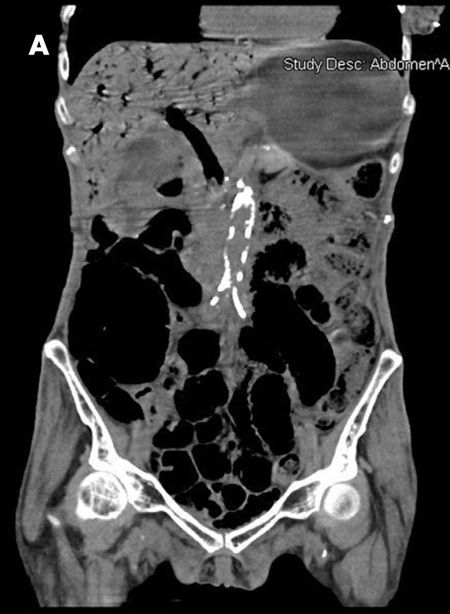

The patient complained of diffuse abdominal pain. She had an erythematous swelling around the right iliac fossa, abdominal guarding, and palpable crepitations. CT scan of the abdomen without contrast showed extensive portal venous air from the small branches in the periphery to the main portal and splenic veins (A and B). Considerable gaseous distention of the small bowel (C and D) and dilated loops of the small bowel were also seen (D and E). These findings were consistent with pneumatosis intestinalis.